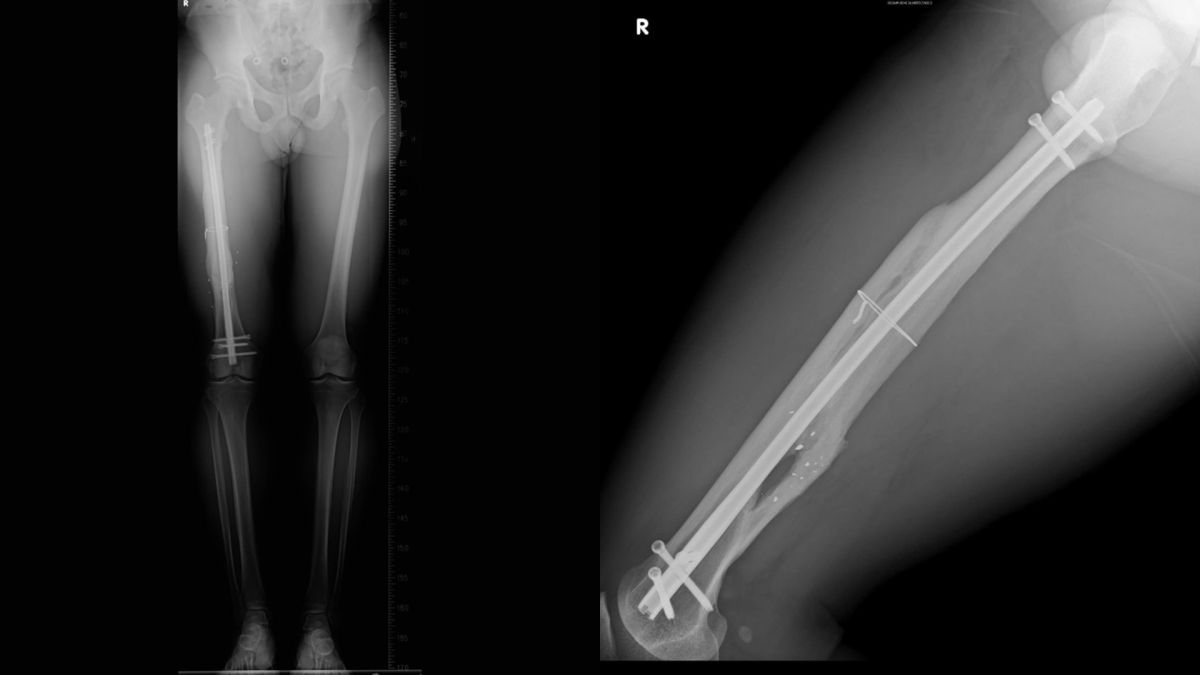

館長在臉書上發文提到「今天是我中槍滿兩年了,回到醫院照片子檢查」,而X光照上顯示,館長右大腿處仍有不少鋼釘,細部照更發現仍有不少子彈碎片殘留在內。

▲知名網紅館長陳之漢2年前曾在林口遭人開槍襲擊。(圖/翻攝臉書飆捍) 館長也感慨表示「雖然天天腳都會痛,但是我還是堅持訓練,反正腿傷問題是無解,命有救回來就好。看裡面還留一堆子彈碎片,就當作是給我自己的紀念品吧」。